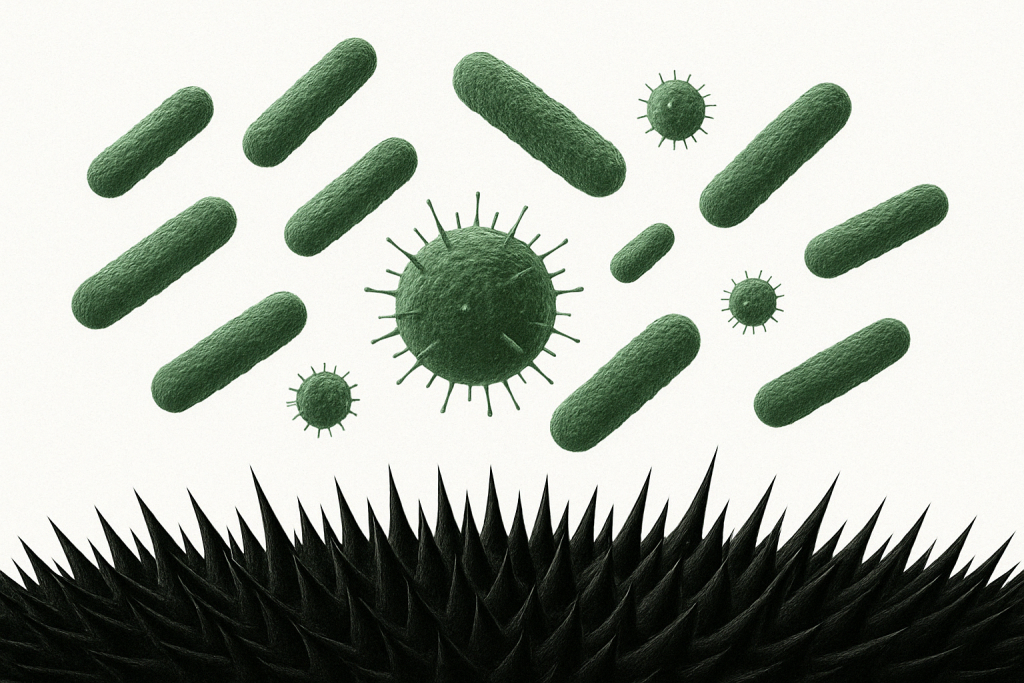

Nanotechnology refers to the use of ultra-small particles measured in nanometers — one billionth of a meter. In MicroSURE, this technology creates a protective layer made of spike-like structures just 4 nanometers in size — far smaller than viruses (~100 nm), bacteria (~1,000–10,000 nm), and fungi (~2,000–100,000+ nm).

Because these nano-spikes are smaller than microbes, no virus, bacteria, or fungus can pass through the MicroSURE layer — and instead, they are physically ruptured and destroyed on contact. At the same time, this barrier supports skin healing, enhances hydration, and provides long-lasting, chemical-free protection — making it ideal for sensitive or compromised skin.

How microSURE™ works

microSURE™ forms a microscopic layer on the affected area that punctures the cell walls of microbes, eliminating them for 8 hours and promoting healing. It is recommended to use microSURE™ 3 times a day until the affected area is recovered, and to continue using it for 1 – 2 weeks after recovery to ensure the microbes do not return.